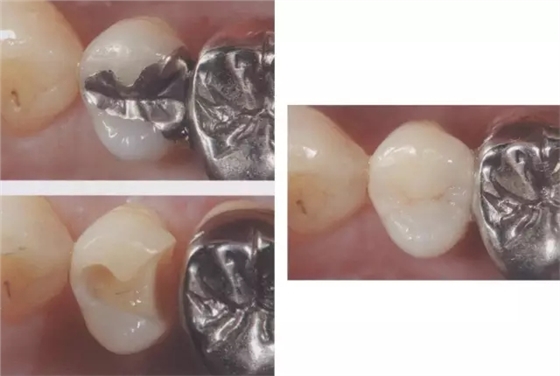

圖3 全瓷嵌體的修復(右56)。鄰接面產生齲齒的情況(上段,中段左),去除齲齒,并佩戴嵌體(下端)。